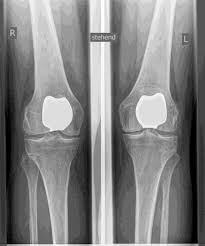

استبدال مفصل العجن (PFJ)

تعمل الرضفة (الرضفة) كعظم معزول في أخدود عظم الفخذ، وباعتبارها المفصل الفخذي الرضفي، تمثل واحدة من الأجزاء الثلاثة لمفصل الركبة.

يمكن أن تؤدي الاضطرابات في الحركة أو عدم الاستقرار وكذلك شكل الرضفة (خلل التنسج) إلى تلف الغضاريف والتهاب المفاصل العظمي المعزول في المفصل الرضفي الفخذي. إذا كانت الأجزاء الأخرى خالية من التهاب المفاصل، فهناك إمكانية لاستبدال مفصل جزئي معزول للمفصل الرضفي الخلفي.